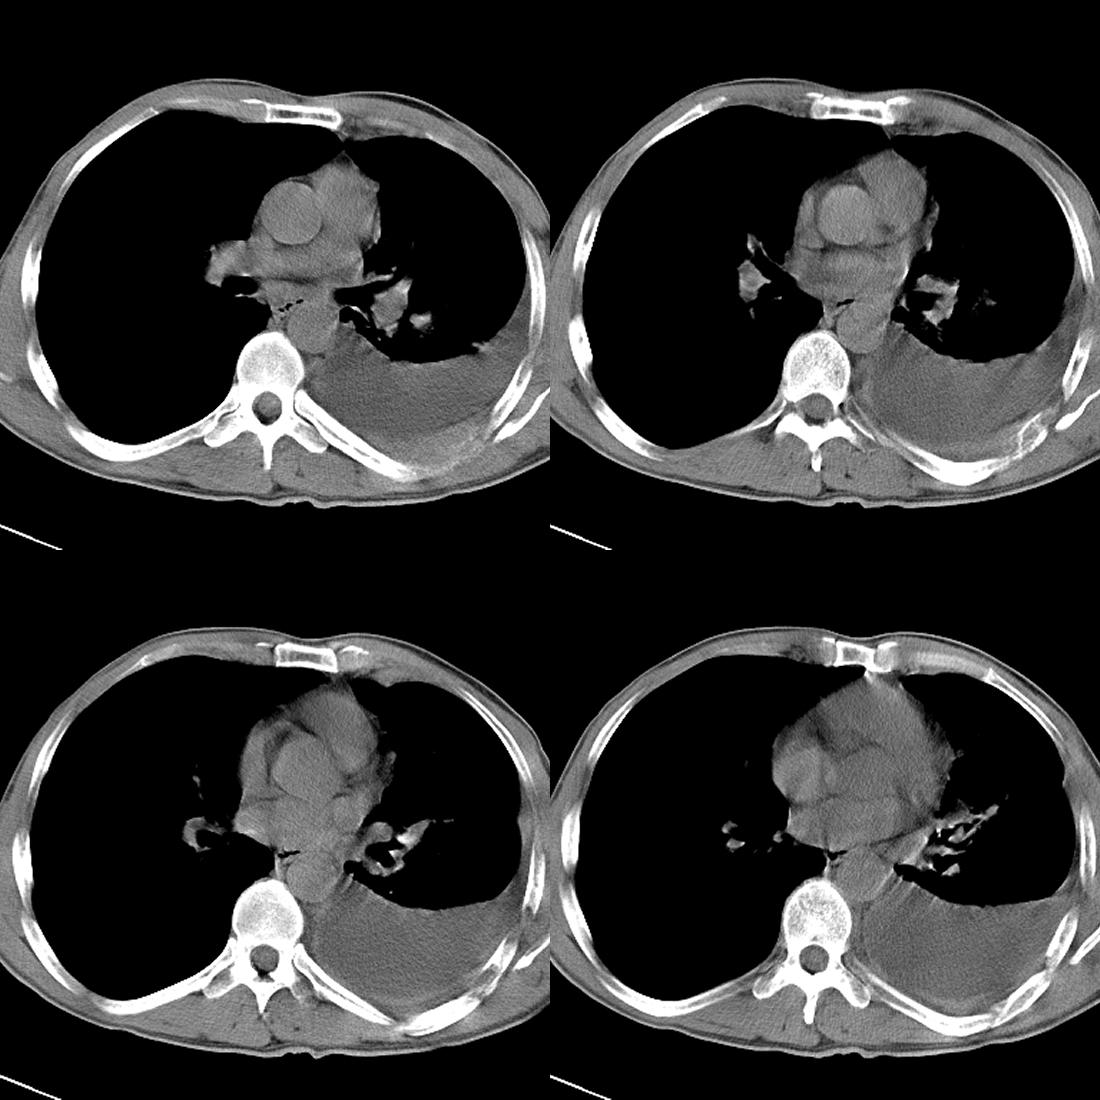

m42y,反复胸背痛数月。无明显的咳嗽、咯痰、咯血症状。

左肺不张 并大量胸腔积液.建议气管镜 除外占位..

左肺上叶周围型肺癌伴肺\\胸膜\\肋骨\\胸椎横突转移,左侧胸腔积液.

左侧椎体、横突、肋骨呈溶骨性破坏,半左侧胸腔中等量积液;左肺尖部可见一肿块影,边界欠清;多考虑恶性骨肿瘤,不除外肺尖部转移性表现可能。

左肺除有肺不张,胸腔积液,尚有斑点、斑片、结节及兔耳征,纤维化等病灶,除考虑除外占位,还应考虑结核所致。。。现在结核病又有泛发趋势。。

左后部肋骨有破坏,应考虑肺癌并转移。。。。